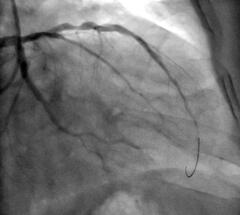

Interventionelle Kardiologie